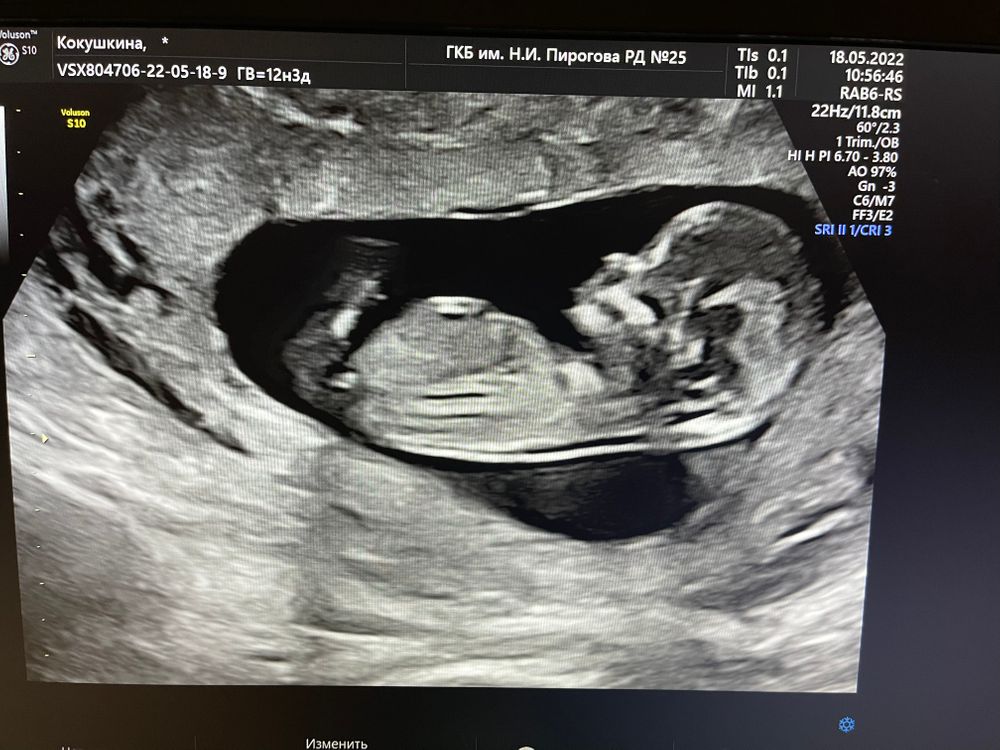

1 скрининг🙌

18.05.2022